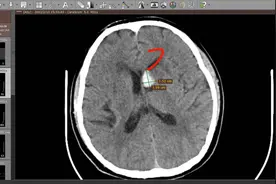

上图为常见颅内出血部位。

脑内、硬膜外血肿出血量(ml)=病灶最大层面长×宽×层间距×病灶层数×0.5(立方厘米),如果层间距是10MM,那么公式可简化为出血量=病灶最大层面长×宽×病灶层数×0.5。测量应不含水肿的范围。硬膜下、脑室内、蛛网膜下腔出血不能用此公式。